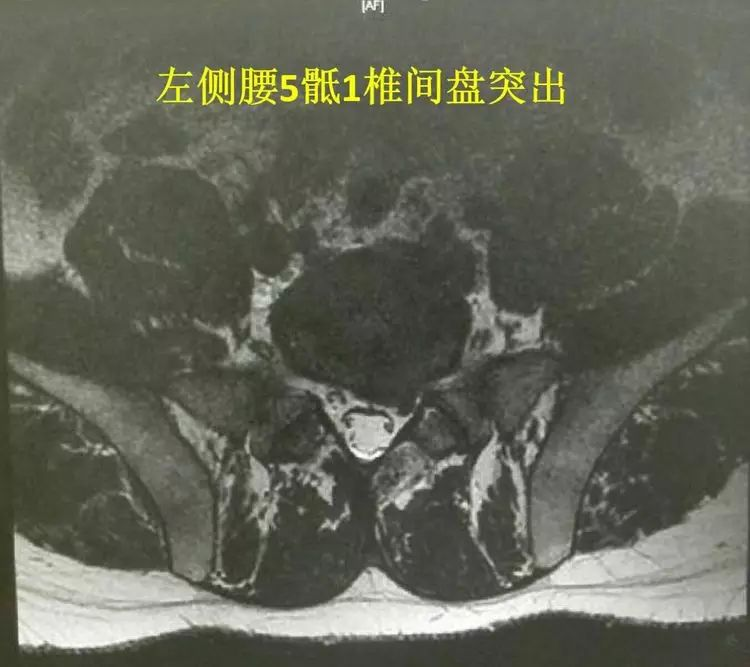

这是一名腰5骶1的椎间盘突出的患者,男性,29岁;从影像上看,突出并不十分厉害,但症状很重,左腿疼痛,药物治疗2周效果不明显。于是选择手术治疗。

我们选择了椎板间入路做经皮穿刺内镜下髓核摘除术。从手术时的场景可以看到,大家的热情很高。还有兄弟科室的兄弟们在场,内心还是有些忐忑的。虽然,每个细节都已经成熟于胸。

第一步C臂定位腰5骶1,全程只透视一次。手术的切口只有6毫米左右。